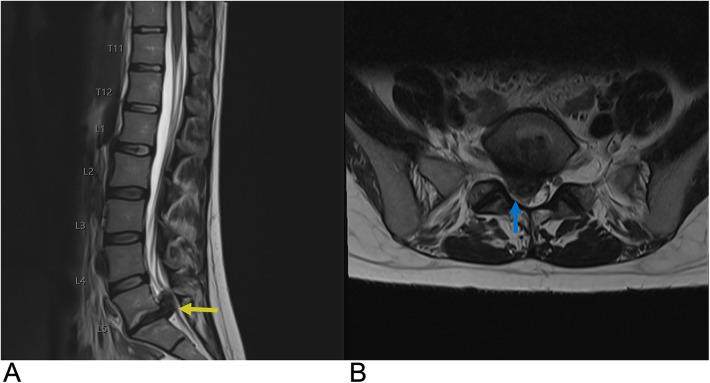

Spinal lesions encompass a diverse range of pathologies, including primary and secondary tumors, infectious processes, vascular malformations, traumatic injuries, and degenerative conditions, each with distinct imaging characteristics crucial for accurate diagnosis and management. Imaging plays vital roles in assessing lesion morphology, anatomical localization, and neurological impact, guiding clinical decision-making and therapeutic planning. This review systematically explores spinal lesions based on their anatomical compartments, highlighting key radiological features and providing a comprehensive reference for radiologists.

脊柱病变包括多种病理情况,包括原发性和继发性肿瘤、感染性病变、血管畸形、创伤性损伤以及退行性疾病,每种病变都具有独特的影像学特征,这些特征对于准确诊断和治疗至关重要。影像学在评估病变形态、解剖定位和神经影响方面发挥着至关重要的作用,指导临床决策和治疗规划。本综述基于解剖分区系统地探讨脊柱病变,突出关键的放射学特征,并为放射科医生提供全面的参考。